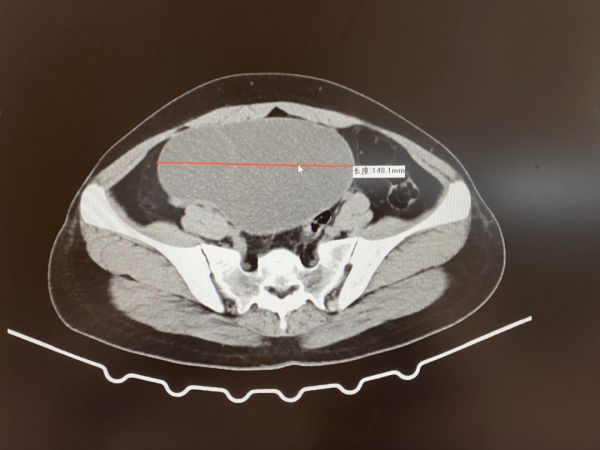

经检查发现盆腔巨大肿块,考虑为卵巢囊肿,不排除恶性。

▲术前检查单

术中,发现该女士盆腔巨大囊性包块约16*15cm,表面光滑,半透明状,包块上缘平脐,来源于卵巢,右侧卵巢已无正常组织。